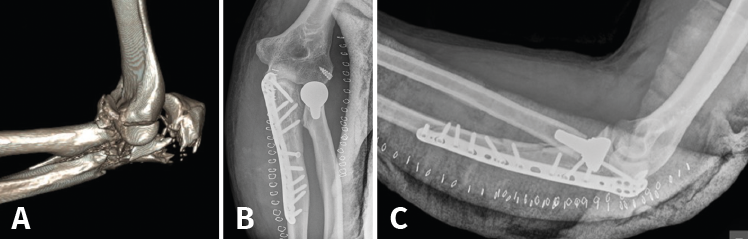

Fractura de Monteggia y lesiones Monteggia-like

Son lesiones poco frecuentes pero complejas. Es esencial una reconstrucción anatómica precisa del cúbito proximal para recuperar la funcionalidad del codo. La restauración anatómica de la longitud y las dimensiones del cúbito será crucial para la congruencia de la articulación radiocapitelar. Una reconstrucción fallida o inadecuada acabará con dolor persistente y una progresiva degeneración de la articulación. Hay que poner especial atención en 2 fragmentos: la faceta anteromedial de la coronoides y la faceta anterolateral del cúbito, junto a la cresta del supinador. La planificación preoperatoria es vital, por lo que recomendamos la TAC con reconstrucción 3D (Figura 9).

Figura 9. A: imagen en 3D de una fractura proximal compleja de cúbito y radio; B y C: radiografías de control tras la cirugía en otro caso de lesión Monteggia-like.

Precisarán siempre tratamiento quirúrgico. Usaremos un abordaje posterior extendido. En las fracturas de Monteggia, el radio recupera normalmente su congruencia una vez que hemos reducido la fractura del cúbito. En las lesiones complejas Monteggia-like, lo ideal es reducir primero el fragmento de coronoides al fragmento cubital distal, ya sea con AK temporales o añadiendo algún tornillo adicional. Es el contrafuerte anterior de la articulación y de más difícil acceso. Luego fijaremos el resto de los fragmentos a la diáfisis con una placa preconformada LCP(41,42,43). Trataremos la fractura de la cabeza del radio mediante osteosíntesis o preferiblemente con una prótesis. Por último, repararemos las lesiones ligamentosas con un anclaje si fuera necesario (Figura 9). Cuando la punta del olécranon es multifragmentaria, un solo tornillo no ofrece fijación suficiente, por lo que hay autores que proponen un cerclaje con sutura de alta resistencia desde el tendón del tríceps para reforzar la síntesis(44,45).